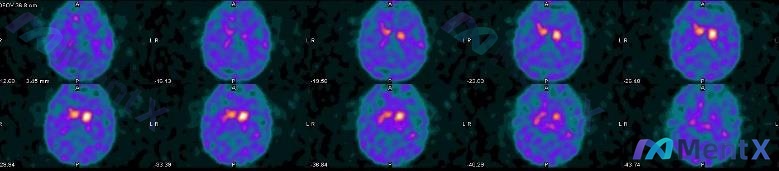

病例资料分享 整理了一份脑部功能影像病例,想和大家讨论一下临床关联。 患者信息:男性,65 岁。 检查项目:脑部多巴胺转运体(DAT)显像(¹²³I-FP-CIT SPECT)。 影像所见: - 双侧纹状体(尾状核和壳核)区域可见放射性摄取。 - 关键异常:右侧纹状体(尤其是壳核)放射性摄取显著低于...